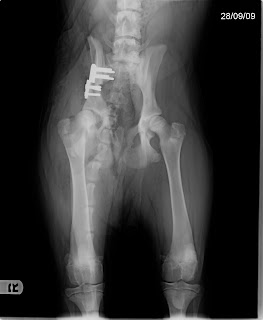

Els tres bisos d'una part de la placa no han aguantat i l'os s'ha desprès de la placa. A continuació podeu veure com vaig quedar després de l'operació i com tinc ara mateix el maluc. No ens expliquem com ha pogut passar, l'Ivan i la Mar m'han tingut molt controlat i no m'han deixat fer gens el burro...

Després de l'operació

Avui (13.10.2009)

He sortit de casa molt content: per fi, després de molts dies, trepitjava el carrer !! Quins olors, quin moviment !! Al arribar al vete, m'han tret tots els punts (no m'han fet gens de mal) i m'han fet la radiografia (sense adormir-me perquè jo soc molt bo i em quedo quietó). Al veure els resultats, la cara de l'Ivan m'ho ha dit tot. Els pocs ànims que teniem, han desaparegut.